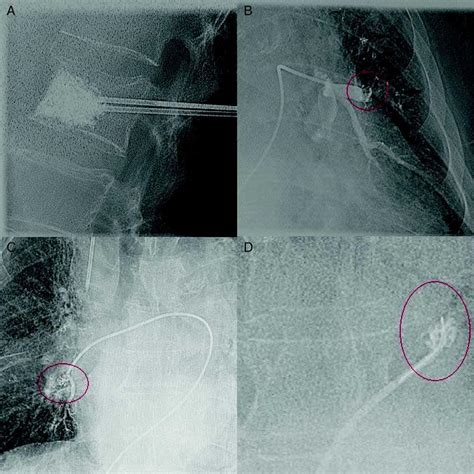

• Angiography: A procedure where a contrast dye is injected to highlight the flow of blood through arteries and veins under X-ray.

• Embolectomy: A surgical procedure to physically remove the embolus from the blood vessel.